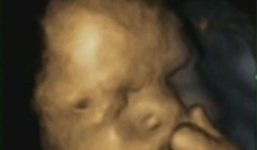

Bất ngờ với hình ảnh thai nhi suy tư trong bụng mẹ